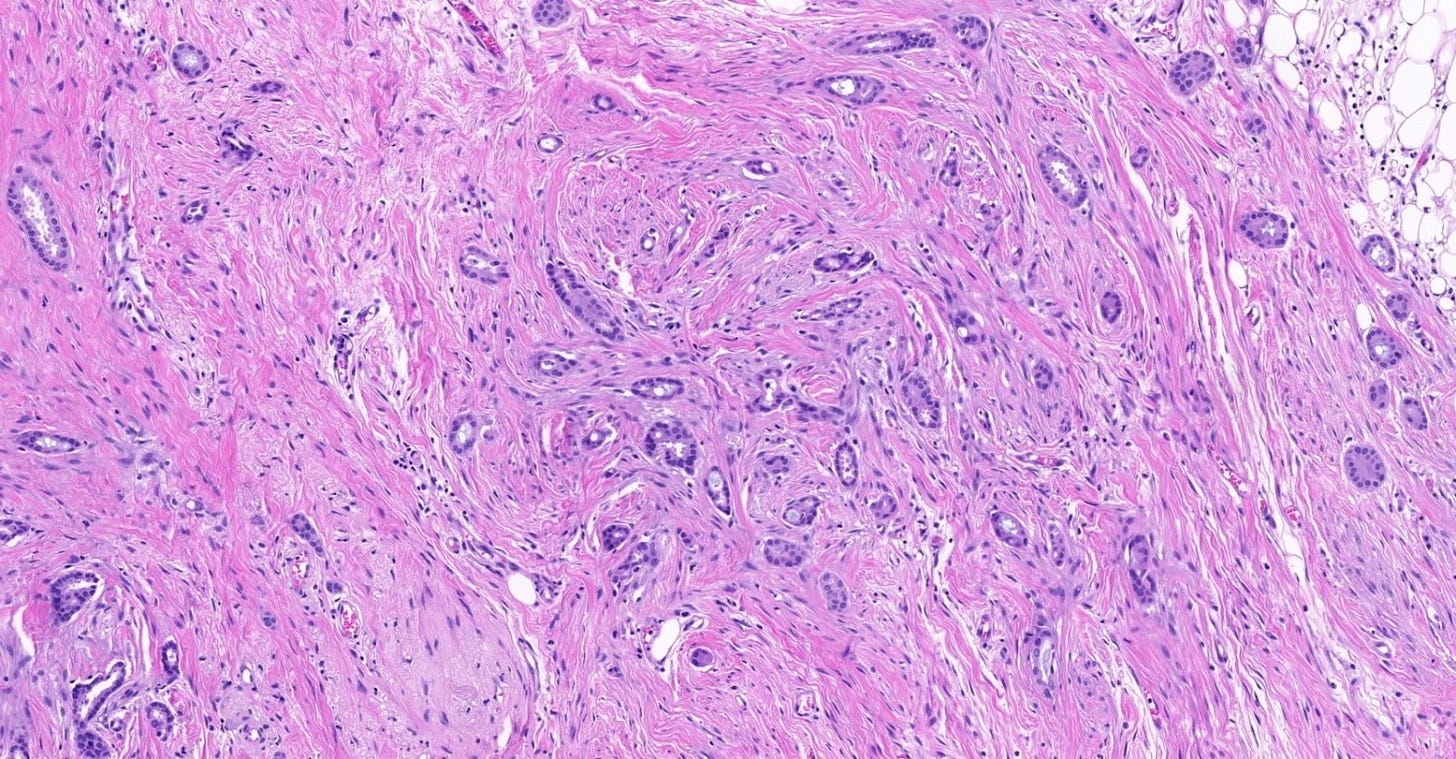

Infiltrating duct carcinoma (IDC) of no special type - microscopic images

Lobular carcinoma

Lobular carcinoma is a common type of invasive breast carcinoma (10% of cases). It is characterized by the loss of cellular adhesion with dyscohesive tumor cells arranged in single file or as individual single cells. The cells show a loss of 16q (the CDH1 gene located at 16q22.1 encodes E-cadherin, essential in forming the adherens junction responsible for cell adhesion). Loss of E-cadherin protein expression by immunohistochemistry is helpful but not required for diagnosis.

Lobular carcinoma of the breast typically presents with vague findings such as thickening, swelling or a poorly defined breast mass. In general, it is more difficult to detect with mammography (due to infrequent calcifications) and more often presents as a larger tumor with nodal involvement compared to invasive ductal carcinoma of no special type. It is more frequently bilateral and multifocal.

A mastectomy may be preferred because of the risk of local recurrence. These patients generally respond better to hormonal therapy compared to those with invasive ductal carcinoma of no special type. However, their response to radiation therapy is comparable, while their response to chemotherapy is less favorable

Classic lobular carcinoma - microscopic images

The premalignant precursors of classic lobular carcinoma are classic lobular carcinoma in situ (classic LCIS), its variants florid LCIS and pleomorphic LCIS, and atypical lobular hyperplasia (ALH).